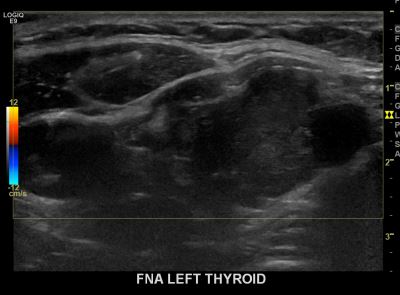

상기환자  외부검사이상소견으로 내원하신 30대 후반 여성분으로 의심스러운 갑상선 좌측혹 세포검사진행후 갑상선암으로 진단되었습니다